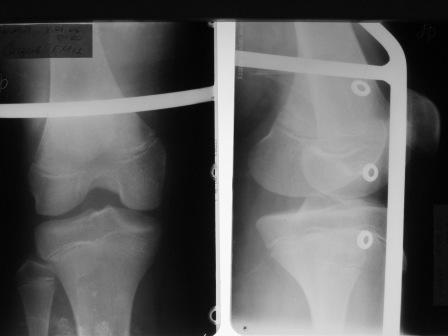

Поступил мальчик 12 лет с переломами диафиза костей обеих голеней. В связи с этим поставлен вопрос, который уже поднимался в узких кругах, но к однозначному решению это не привело. Можно ли в данном случае применить ЗИО с блокированием? Если использовать классическую точку входа над бугристостью и избежать блокирования в зонах роста повлияет ли это рост кости? Как с этим обстоят дела у иностранных колег?

Данных в поддержку блокируемого штифтования большеберцовой кости у детей не найдено (в отличие от бедра,встречаются статьи-от 6! лет). Зато среди причин GENU RECURVATUM указывается скелетное вытяжение в области бугристости большеберцовой кости, при незакрытой зоне роста. На предоставленых снимках зона роста апофиза закрыта шиной Беллера.